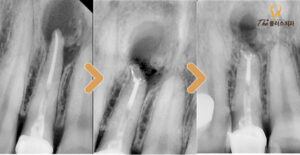

먼저 잇몸을 박리하여 염증을 제거한 후

염증이 염증이 발생된 치근을 절제하게 되는데,

염증 제거 후 심한 뼈손실이 있을 경우

치료 중 뼈이식을 함께 진행하기도 합니다.

환자분께서는 뼈이식은 따로 진행하지 않고

뿌리 끝에 세균이 재 감염되지 않도록

끝부분을 MTA라는 특수한 충전 재료를 통해

마무리한 후 경과를 지켜보기로 하였습니다.

치근단 절제술의 경우,

예후를 지켜보기 위해 정기적으로

검진하는 과정이 꼭 필요합니다.

이를 통해 염증 조직들을

제거하고 난 후의 잇몸뼈가 차오르는 과정을

꼼꼼히 살펴보며 상태를

확인하는 과정을 거치게 됩니다.